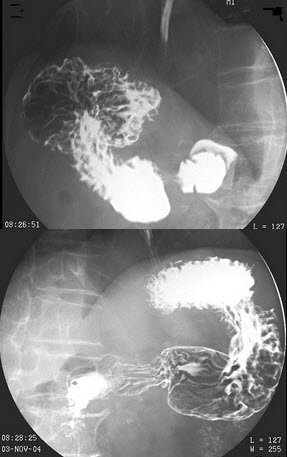

79、单项选择题

男,78岁,上腹痛1月余,返酸,无嗳气,空腹加重。体检:上腹压痛,结合图像,最可能的诊断为()

A.正常表现

B.慢性胃炎

C.胃癌

D.十二指肠憩室

E.十二指肠占位